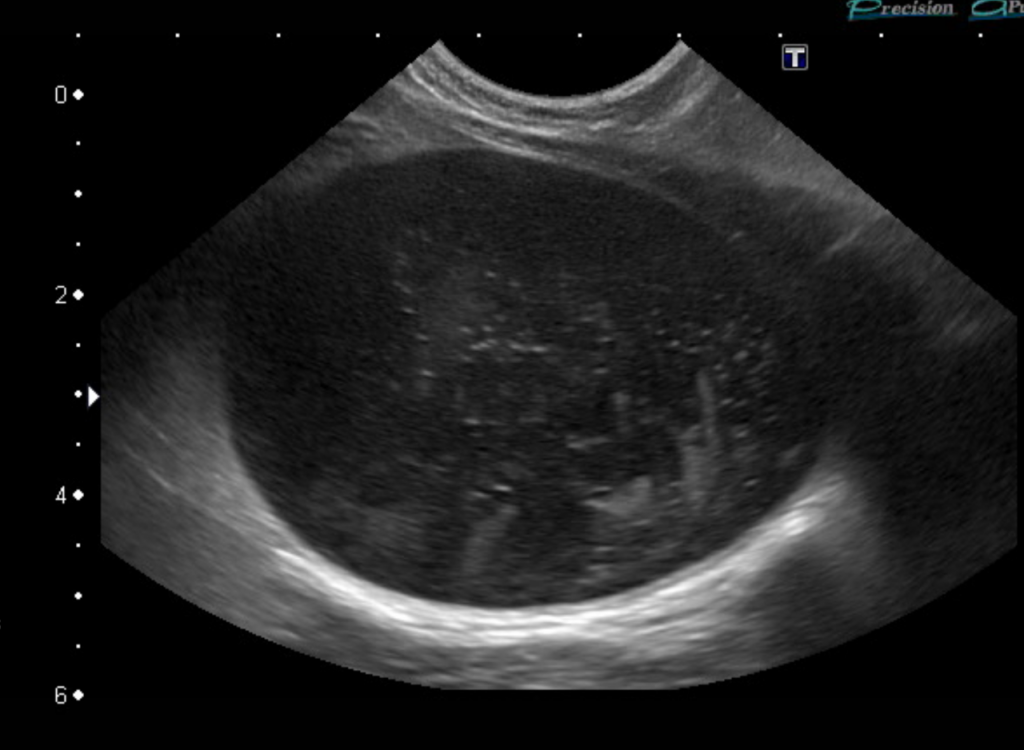

膀胱のエコー画像です。膀胱内に明らかな結石や腫瘍は見られませんが、膀胱内に細かい砂状構造物が多数見られます(白い点々)。

これらが集まって尿道を塞いでいると予想されました。